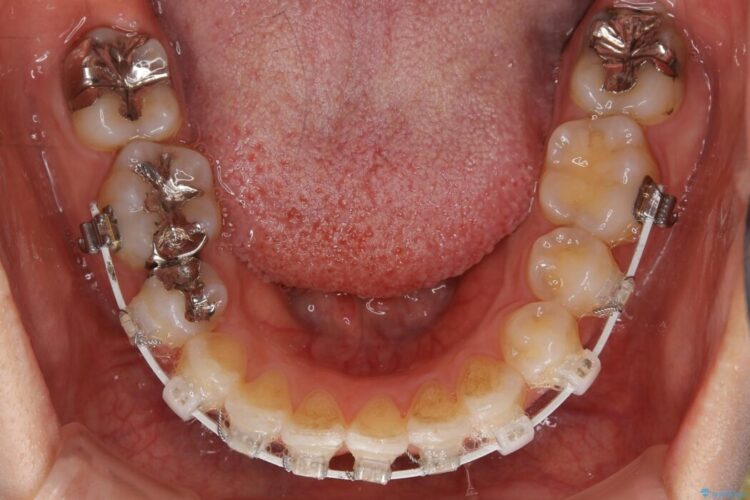

【20代女性】矯正治療後の後戻り

- 患者様:20代女性

- 治療期間:1年

- 矯正装置:審美装置

- 概算治療費:66万円

抜歯矯正後の後戻りについてご相談にいらした患者様です、

いつもでしたらマウスピース矯正をおすすめするのですが、自己管理の煩わしさから、目立たないワイヤー装置にて矯正治療を行うこととしました。

後戻りの程度としては軽度なので、治療期間としては短く終えることが出来ました。

前歯の正中線も改善され大変満足していただきました。